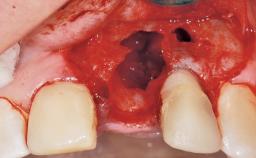

A 42-year-old female patient was referred to our clinic at the School of Dentistry of the University of São Paulo in November 2004, presenting a deficient restoration in the upper left central incisor. The clinical examination revealed no gingival retraction or any signs of gingival inflammation and, therefore, previous periodontal treatment was not considered. The patient presented a high lip line at full smile and a thin tissue biotype. This combination characterized a high-risk situation from an anatomic point of view, which required careful preoperative planning and cautious surgical execution.